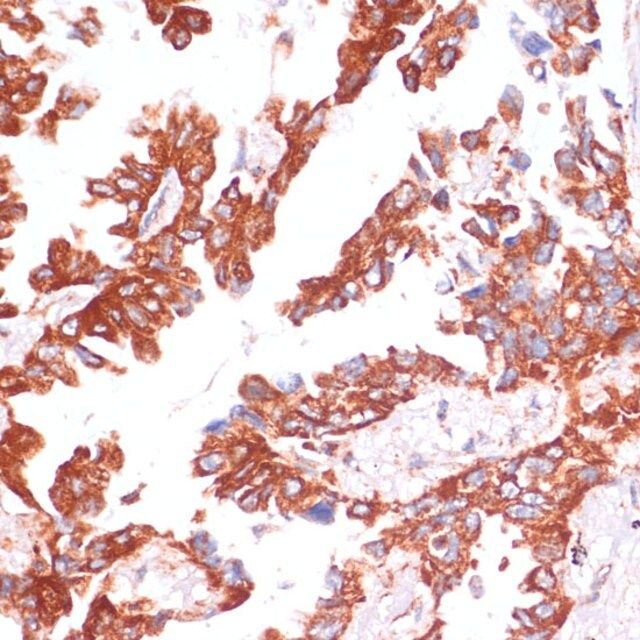

| technique(s) | immunofluorescence: 1:50-1:200 immunohistochemistry: 1:50-1:200 western blot: 1:500-1:2000 |